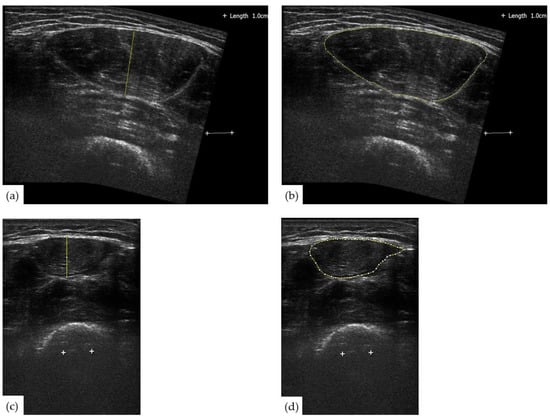

2.2. Ultrasonography